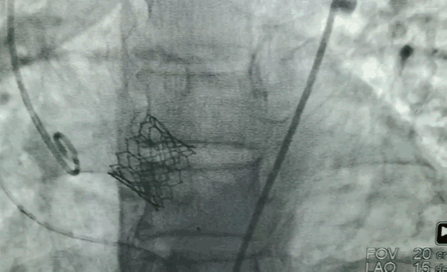

第一个病人的特点是,需要在解决主动脉瓣问题的同时,解决冠状动脉的问题。针对病人特点,来永强教授和周玉杰教授提前在网上进行了会诊,设计一站式杂交手术,前降支和右冠各放一个支架,同时用SAPIEN 3瓣膜进行TAVR手术。

“相当于经皮主动脉瓣膜植入术中同时行PCI手术,不开胸,对患者来说是获得最大的效益。”周玉杰教授表示,TAVR同期行PCI,这两个手术合在一起,带来了病人的双获益。